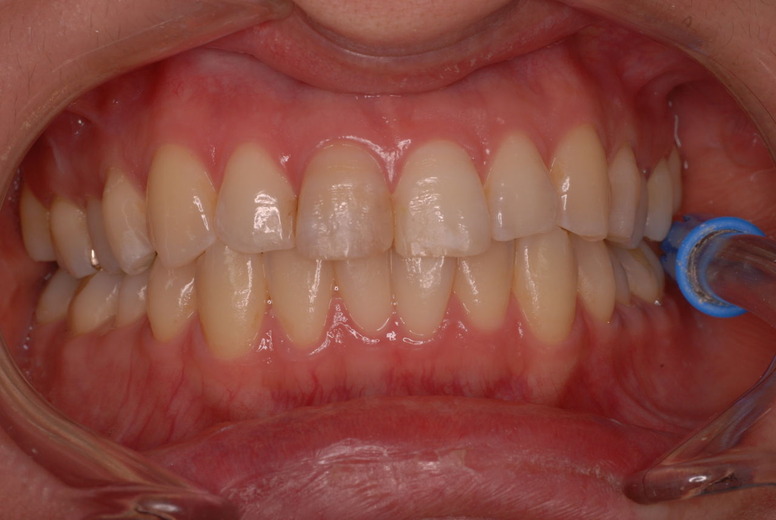

入れ歯の話から入りました。色々不満で注文があるようです。でも話が一段落して口腔内を調べると殆どの歯が重症で抜けそうな歯だらけなのです。

ご自分でやられても歯茎から血が出ないと話をされていましたが、私がブラシを当てると悲惨な状態であることがわかりました。